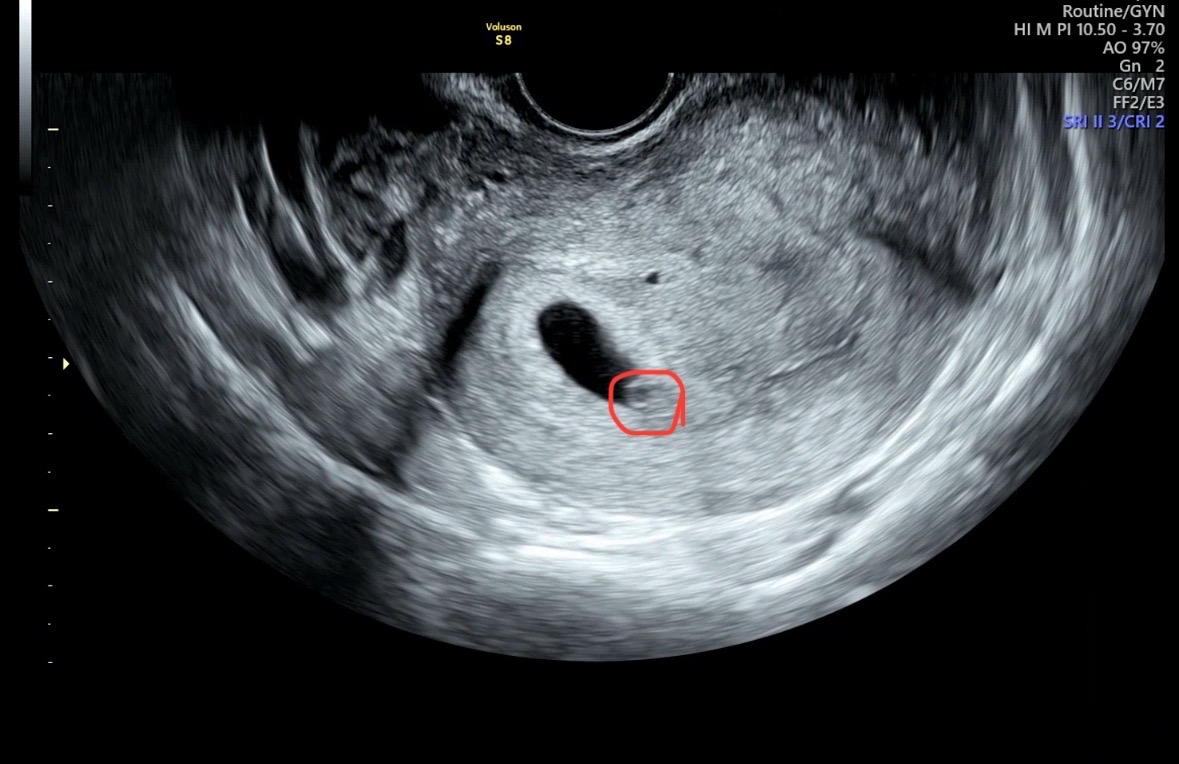

임신6주 애기가 너무 벽에 붙어있데요...

6주0일에 본 초음파인데 심장소리는 124회로 들리는데 아기가 너무 붙어있어서 잘 안보인데요...괜찮은거겠죠? 혹시 저렇게 붙어있으면 잘 안자랄수도 있나요?